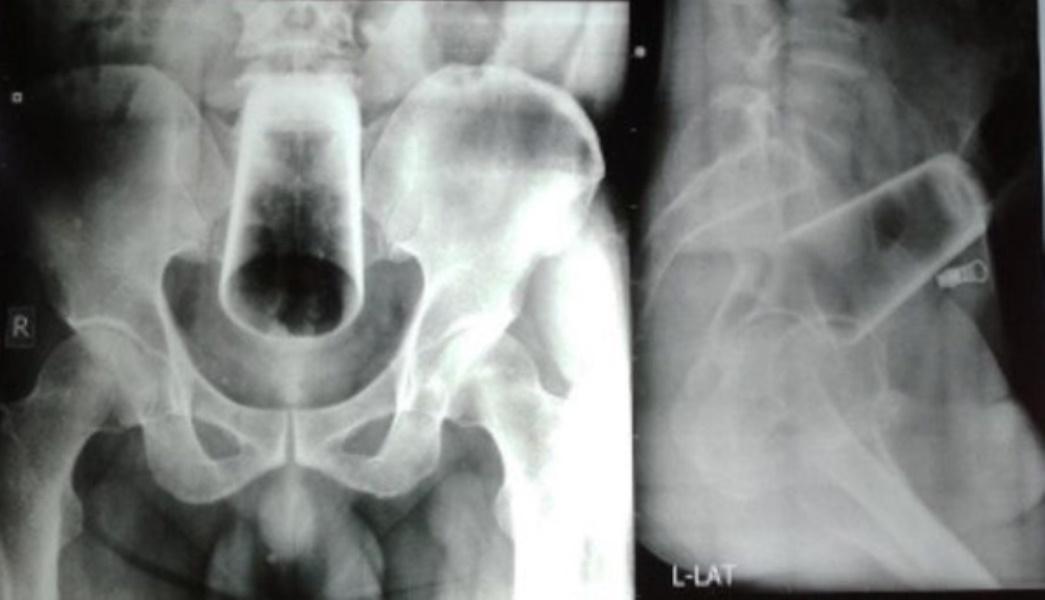

綜合報道,自加德滿都一名47歲男子因連續3日無法排便,到醫院求診,他向醫生承認自己酒醉後將玻璃酒杯塞入肛門,結果無法取出。男子表示,肛門疼痛,但腹部並無出現腫脹,肛門部位也沒有受傷或出血。醫生以X光發現一隻12厘米高的玻璃杯,卡在直腸和結腸,斷定無法徒手取出,亦不可能擊破破璃,只能開才取出。

這宗離奇的病例被紀錄在《尼泊爾醫療學會》(Journal of Nepal Medical Association)的期刊。醫生表示,男子的精神和心理狀態都非常良好,術後一周出院,兩個月後的復診也未出現問題。不過醫生提到,大多數異物卡在直腸內的病例都發生在30至40歲的男性身上,異物分別有汽水樽、酒樽、木製或橡膠物品等都曾發現過,且大多數患者在塞入異物時,都已呈酒醉狀態。